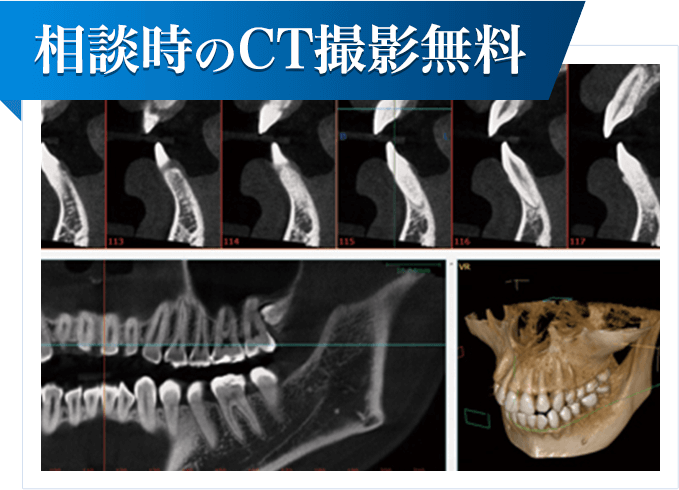

写真のように、CTで見ると、骨吸収の様子が良く分かり、下顎骨の中を通る神経近くまで骨がありませんでした。

写真のように、CTで見ると、骨吸収の様子が良く分かり、下顎骨の中を通る神経近くまで骨がありませんでした。

さらに、CTで、別な方向から見ると、黄色矢印のように骨が吸収されていて、緑色矢印で示される神経の通る管に迫り、インプラントが埋入できるような骨量はありませんでした。

さらに、CTで、別な方向から見ると、黄色矢印のように骨が吸収されていて、緑色矢印で示される神経の通る管に迫り、インプラントが埋入できるような骨量はありませんでした。

CTで見ると、骨が薄いのが良く分かります。黄色の矢印の部分、白く写るのが骨で、矢印のある黒い部分が上顎洞という空洞です。

CTで見ると、骨が薄いのが良く分かります。黄色の矢印の部分、白く写るのが骨で、矢印のある黒い部分が上顎洞という空洞です。

写真は初診時の患者様のレントゲン写真です。左右とも、上顎第一大臼歯を失っていました。通常のレントゲン写真では、骨量が十分かと思われましたが、CTを撮影してみると、黄色の矢印部位、左側では、少し骨の高さが足りませんでした。

写真は初診時の患者様のレントゲン写真です。左右とも、上顎第一大臼歯を失っていました。通常のレントゲン写真では、骨量が十分かと思われましたが、CTを撮影してみると、黄色の矢印部位、左側では、少し骨の高さが足りませんでした。

CTを撮影して、測定すると、右側はギリギリ10mmぐらいの高さで、左側は6mmほどしかありませんでした。

CTを撮影して、測定すると、右側はギリギリ10mmぐらいの高さで、左側は6mmほどしかありませんでした。

確実な治療を行うために、口腔内の状態、顎骨の状態等につき詳しく検査します。顎骨の状態を精密に把握するために、全例にCT撮影を行います。 全身状態の把握も重要で、必要な場合は、他科の受診、主治医があれば情報提供をお願いしています。